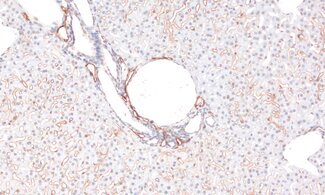

Detection of nuclear Lamin B1 in a formalin fixed paraffin embedded (FFPE) mouse lung section.